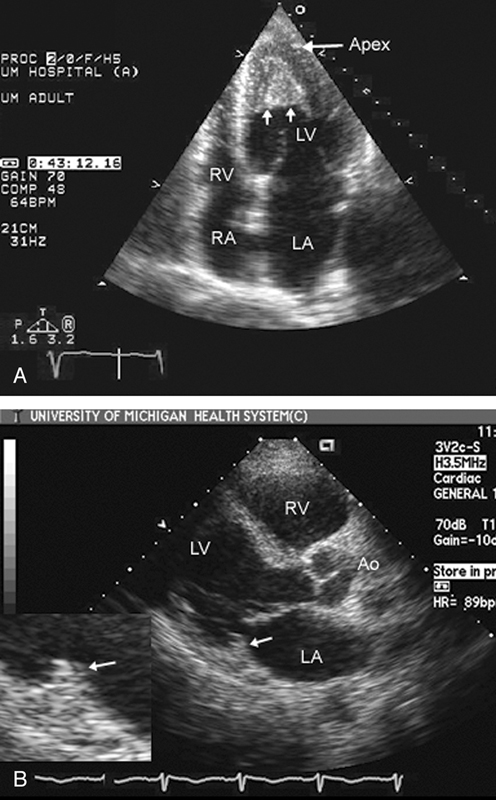

فحوصات تشخيصية لبعض امراض القلب والشرايين التاجية